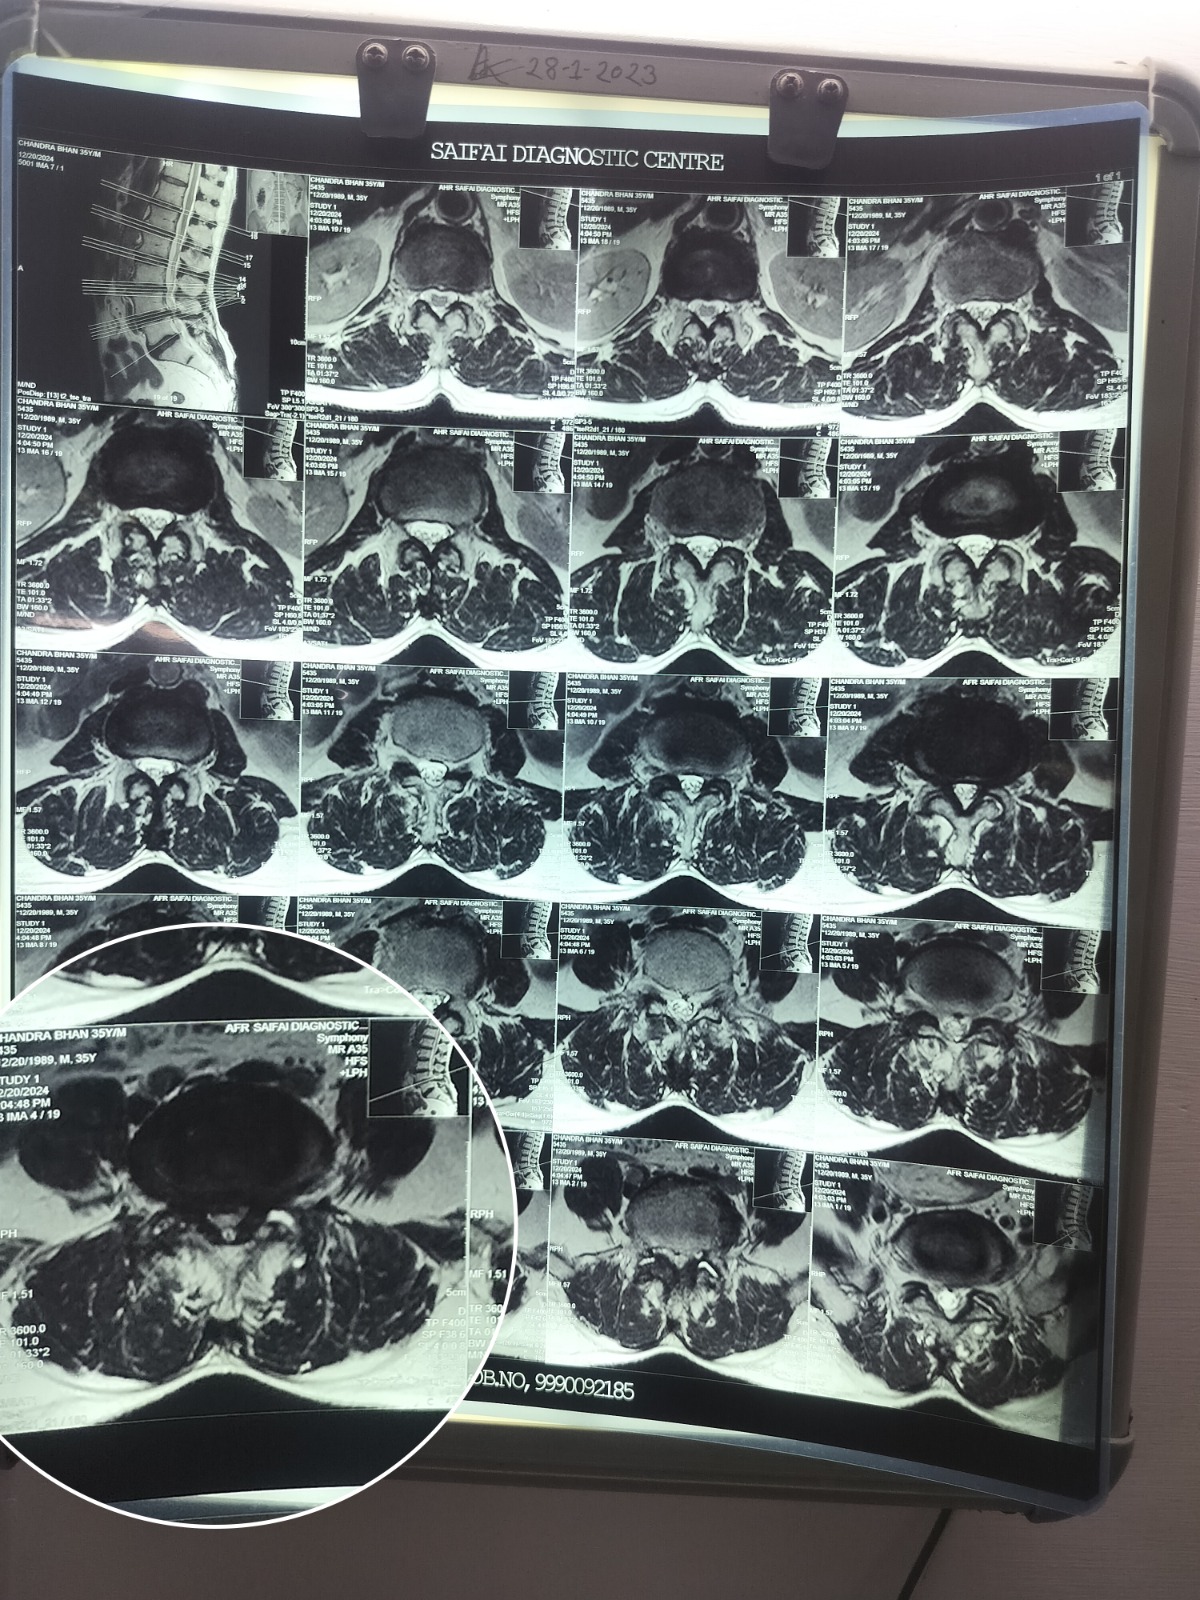

- We evaluate the patient first clinically and then radiologically with MRI and ascertain the position of disc.